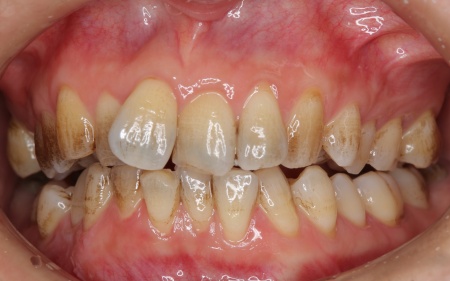

拝見したところ、歯が全体的にずれたりねじれたりして生えており、歯並びがデコボコしていました。 また、数本の歯にはプラスチックの詰め物が装着されていましたが、経年的な劣化により歯との間に段差が生じています。これも噛み合わせのバランスを崩す原因のひとつになっていると考えられました。 歯並びや噛み合わせの乱れをこのまま放置すると、歯磨きがしにくくなり虫歯や歯周病のリスクが高まるほか、特定の歯に強い力がかかり続けることで将来的に歯の寿命に影響を及ぼすおそれもあります。

以上のことから、見た目だけでなくお口全体の噛み合わせまで考慮した治療が必要と診断しました。 |

診断結果を踏まえ、まずはワイヤー矯正で歯並びと噛み合わせを整え、その後に形が変化している歯や劣化した詰め物を白いセラミック素材で作り直す治療計画を提案し、同意いただきました。 この治療方法であれば、歯を動かして噛み合わせの位置関係をしっかりと整えたうえでセラミックによる修復治療を行えます。また金属を使用しない白い素材を用いるため、見た目の違和感を抑えられます。 また、下の左右に半分埋まっている親知らず(第3大臼歯)があるため、矯正治療の際に抜歯する必要があることをお伝えし、ご了承いただきました。 まず親知らず2本を抜歯し、ワイヤー矯正治療から開始します。

治療前